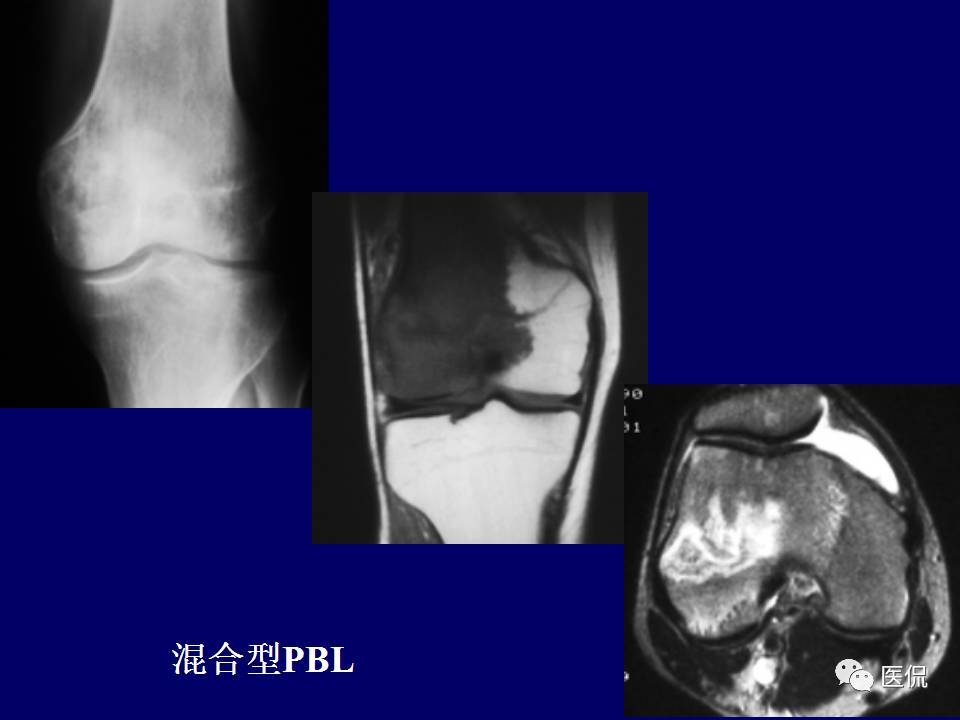

原发性骨淋巴瘤,是一种少见肿瘤。平片上干骺端单发、浸润性骨质破坏、层状骨膜反应+MR上骨髓侵犯、软组织肿块+年龄>30岁均可高度提示,影像学区分原发和继发PBL比较困难。更多知识,请往下看~